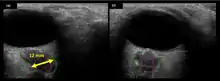

Figure 5: On-orbit ultrasound of posterior orbit of the fourth case of visual changes from long-duration spaceflight. In-flight ultrasound image of the right eye showing posterior globe flattening and a raised optic disc consistent with optic-disc edema and raised ICP.

Figure 6: On-orbit ultrasound of optic nerves of the fourth case of visual changes from long-duration spaceflight. In-flight ultrasound shows proximal kinking and increased optic nerve sheath diameter (ONSD) of approximately 12 mm that is consistent with raised ICPs. Optic nerve shown in purple and the ONSD in green.